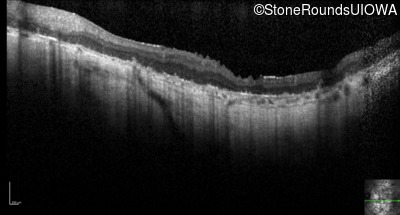

Optical Coherence Tomography - Right - Hand Motion sc

Exemplar / OCT Stack

OCT Stack